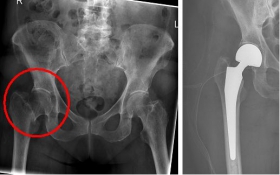

Picture: This picture shows the treatment of a severely displaced fracture with a so-called duo head prosthesis. The acetabulum was left here.

Picture: In this case, there was already a wear of the hip joint and the affected patient was relatively young, so that a cement-free total endoprosthesis (TEP) of the hip was selected for the treatment of the femoral neck fracture. Here, in addition to the femoral head, the acetabular cup was replaced by an implant.